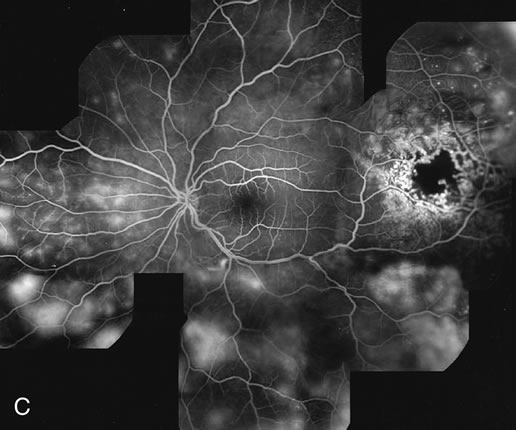

PCV is characterized by the presence of dilated, choroidal vascular channels ending in orange bulging polyp-like dilations in the peripapillary and macular area. Associated features are recurrent subretinal hemorrhage and vitreous hemorrhage, relatively minimal fibrous scarring, absence of retinal vascular disease, pathologic myopia, and signs of intraocular inflammation. FA demonstrates the presence of the dilated vascular channel (Fig. 14 and 15). However, the presence of blood and exudation may block the details of the choroidal circulation on the angiogram. In these cases, ICG angiography can better demonstrate the presence of a distinct network of vessels within the choroid because the larger choroidal vessels are filled with dye.

Fig. 14. A. Color photograph of the right eye shows a ramified pattern of choroidal vascular abnormality irradiating from the peripapillary area toward the macula. The dilated vascular channels end with bulging polyp-like structures. A larger, orange, saccular dilation is seen inferior to the macula (white arrow); leakage of fluid from this vascular abnormality results in serosanguineous pigment epithelium detachment (black arrows). B. The corresponding fluorescein angiogram composite highlights the vascular lesion in the peripapillary area and the serosanguineous detachment of the pigment epithelium that extends inferiorly and temporally off the macula.